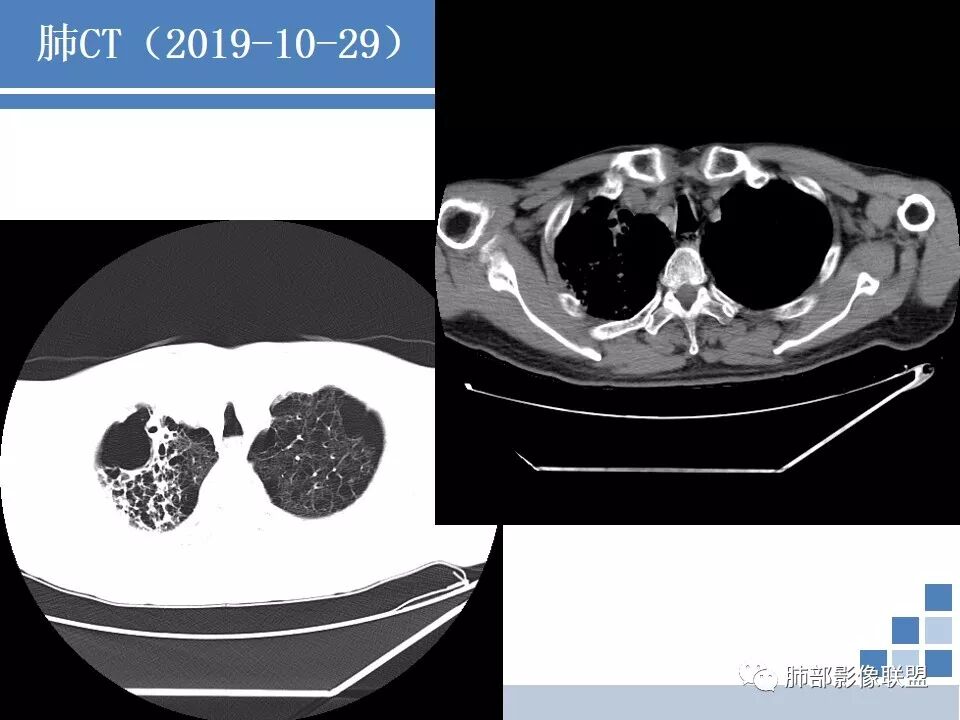

临床:发热咳嗽一周,血沉、CRP高,低氧血症,结核伽马干扰素阳性。抗生素治疗无效;

CT:肺气肿肺大泡背景,右上肺磨玻璃及实变影,10天及20天复查影像明显进展至两肺更大范围,伴右侧胸水。

12.30晨读:男性,有老年痴呆史(程度如何?),咳嗽咳痰发热1周,查体见喘息貌。血气分析:缺氧明显,过度通气,肿瘤标记物:CEA、CA199升高;白介素6升高。10.29第一次胸部CT:肺气肿、肺大泡背景,肺气肿背景感染改变,未见明显肿块及结节影,所以上面肿瘤标记物升高是坑?还是肺外有恶性肿瘤?抗感染治疗症状无改善,复查CT见病灶进展。临床最怕碰到这种病人。考虑感染性病变。结构性肺病相关性感染病原体:环境分枝杆菌、丝状细菌、烟曲霉、葡萄糖非发酵菌……太难了,敬候各位老师的精彩分析。